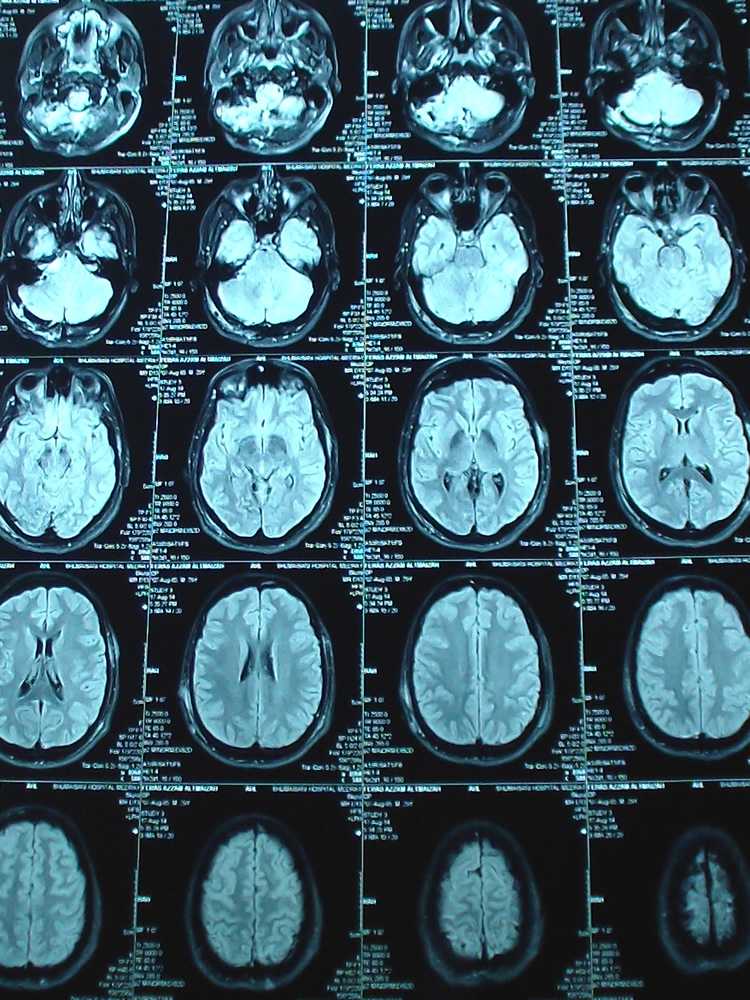

This case demonstrate that MRI must be performed at regular basis after surgery to prevent escalating complications, which could evolve several hours after surgery Fig 3-4.

Figure-3: TW2 MRI done 2 days after surgery, demonstrating the progression of edema at the resected last piece of the tumor. which was severely adherent to the medullo-pontine angle.